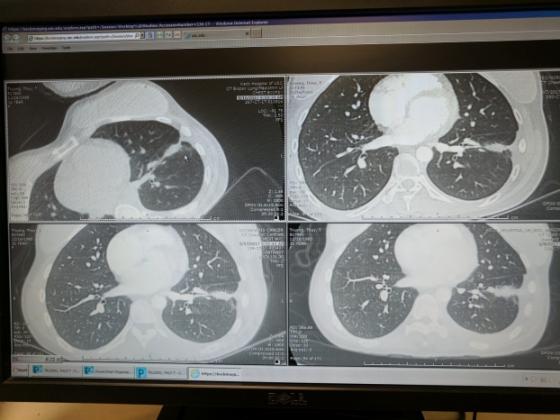

Ảnh chụp phổi của Thuỷ Muối vào tháng 8/2017